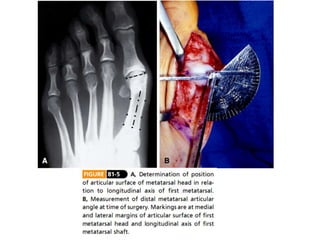

9.- colocax kirschner:1 -1.3 cm proximal borde medial de la superficie articular 10.- angulación de 30 ° dorsalmente (entre ellos 60 -70°)

11.- traslada lateralmenteel fragmento cefálico

12.- se fijacon un kirschner 13.- colocación de un tornillo interfragmentario.

14.- se resecala parte sobresaliente del metatarsiano proximal. 15.- se completa la osteotomía 16.- mientras se coloca el vendaje se coloca el dedo gordo en la posición correcta 17.- osteotomía de chevron ( v invertida)